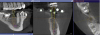

Fig. 2 and Fig. 3 The implant being placed virtually relative to available bone, contacts, and final restoration.